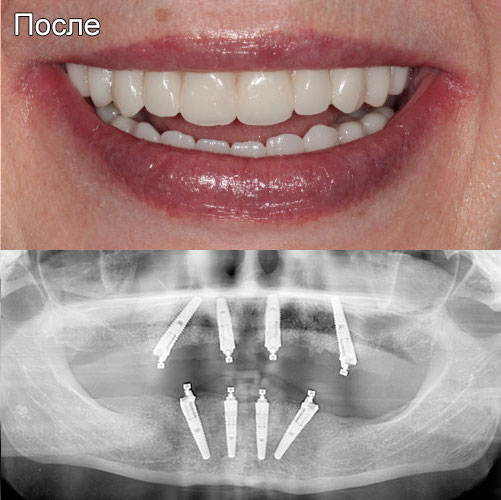

Пример после выполнения операции и установки протеза

Протокол «Все-на-4х» позволяет проводить операцию имплантации с немедленной нагрузкой. Что это значит? Для пациентов это хорошая новость в связи с тем, что практически сразу после проведения операции возможно изготовить временный акриловый протез и уже сразу установить его пациенту. Все это происходит в течение трех дней после основной процедуры.

Пациент уже начинает привыкать к новым зубам, жевать, постепенно повышая нагрузку и улыбаться.